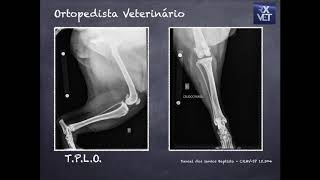

Avaliação Radiográfica do Joelho - Daniel dos Santos Baptista (CRMV-SP 15.304)

22:10

Avaliação Radiográfica do Joelho - Daniel ...

Raiox Vet Oficial

5,432 views